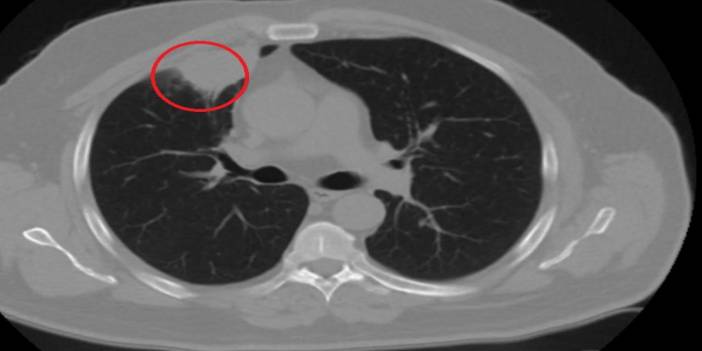

Türkiye'de her yıl 40 bin yeni akciğer kanseri tanısı konuluyor

Dünyada ve ülkemizde hızla yaygınlaşan akciğer kanseri erkeklerde prostat, kadınlarda ise meme kanserinden sonra en sık görülen ikinci kanser türü. En önemli nedeninin sigara olarak gösterildiği akciğer kanseri, özellikle nefes darlığı, hırıltı, ani kilo kaybı ya da çeşitli ağrılarla kendini gösterebiliyor. Göğüs Cerrahisi Uzmanı Prof. Dr. Cemal Asım Kutlu, son yıllarda hiç sigara içmeyen kişilerde görülen akciğer kanserindeki artışa dikkat çekerek “Risk oluşturan maruziyetlerde ikincil içicilik olarak adlandırılan durum ilk sırada görülmektedir. Bu terim önceki yıllarda kullanılan pasif içicilik olarak adlandırılan durumu ifade etmektedir” dedi.

Prof. Kutlu, akciğer kanserinin risk faktörleri arasında ilk sırada gelen tütün kullanımına dikkat çekerek “Dünyanın belli bölgelerinde tütün kullanma sıklığı azaldıkça akciğer kanser tanılarının azalması yıllar öncesinden bilinen tütün-akciğer kanseri ilişkisi için önemli bir örnektir” diye konuştu. Kutlu, özetle şunları söyledi: “Ancak bu azalmayla birlikte son yıllarda hiç sigara içmeyen kişilerde görülen akciğer kanseri tanılarındaki artış dikkat çekmeye başlamıştır. Bu grup olguların tütün kullanan grupla olan ortak noktaları veya farklılıkları konunun uzmanları açısından ilginç bir araştırma konusudur. Tıbbi literatüre göre ‘hiç tütün kullanmamış’ olarak kabul edilen kişi, tüm yaşamı boyunca toplam olarak 100 adetten daha az sigara içmiş kişidir. Erkekler arasında tanı alan akciğer kanseri olguları içinde tütün kullanmamış kişilerin oranı yüzde 10-20 arasında değişirken, bu oran kadınlar arasında yüzde 50’dir. Doğal olarak, tütün kullanımının oluşturduğu risk gibi bilinen diğer risk faktörlerine maruziyetin bu grup hastalar için de önemli olduğu düşünülmektedir. Risk oluşturan maruziyetler nelerdir diye bakarsak ‘ikincil içicilik’ olarak adlandırılan durum ilk sırada görülmektedir. Bu terim önceki yıllarda kullanılan ‘pasif içicilik’ olarak adlandırılan durumu ifade etmektedir. Yani tütün kullanmayan bir kişinin içinde bulunduğu sosyal ortam sebebiyle sürekli olarak dumana maruz kalmasını ifade eder. Yapılan çalışmalar, tütün kullanmayan grubun yüzde 15-35’inde hastalığın sebebinin ikincil içicilik olduğunu göstermiştir. Bu konuda daha da detaya girersek, hiç sigara kullanmamış bir kadın sigara içen bir erkekle evli olduğunda akciğer kanserine yakalanma riskinin yüzde 27 arttığını görebiliriz. ”